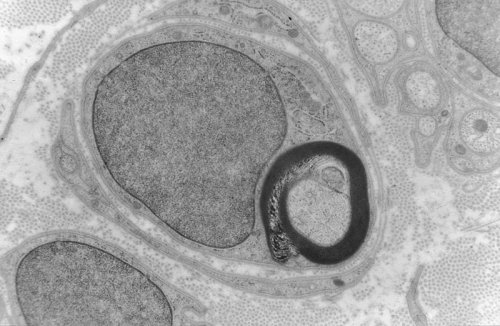

Alors je ne sais pas si tu fais référence à cette partie "Un axone par définition dans le SNP va être recouvert d’une gaine. Cette gaine dérive de la crête neurale.

Cette gaine est recouverte par les cellules de Schwann" mais si c'est le cas oui oui c'est bien la gaine de myéline^^ !

Et étant donné que la myéline est formée par la cellule de Schwann qui embrassent l'axone, tu vois bien qu'après la gaine de myéline est recouverte par la cellule de schwann !

(Ex: sur la photo c'est une fibre en cours de myélinisation)

Et en effet à part la gaine de myéline je ne pense pas qu'on puisse parler véritablement de gaine et ce qui concerne l'endonèvre/le périnèvre/ l'épinèvre/le paranèvre car le Pr. Philip les qualifie de capsules conjonctives, et non pas de gaine ;)